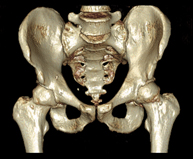

- Pelvic bone CT

Radiological examination based on an X-ray system and detectors that rotate around the patient, reconstructing the images by computer (multidetector computed tomography - MDCT) to study the bones, muscles and joints of the pelvis.

- Hip CT

Radiological examination based on an X-ray system and detectors that rotate around the patient, reconstructing the images by computer (multidetector computed tomography - MDCT) to study the bones, muscles and joints of the hips.